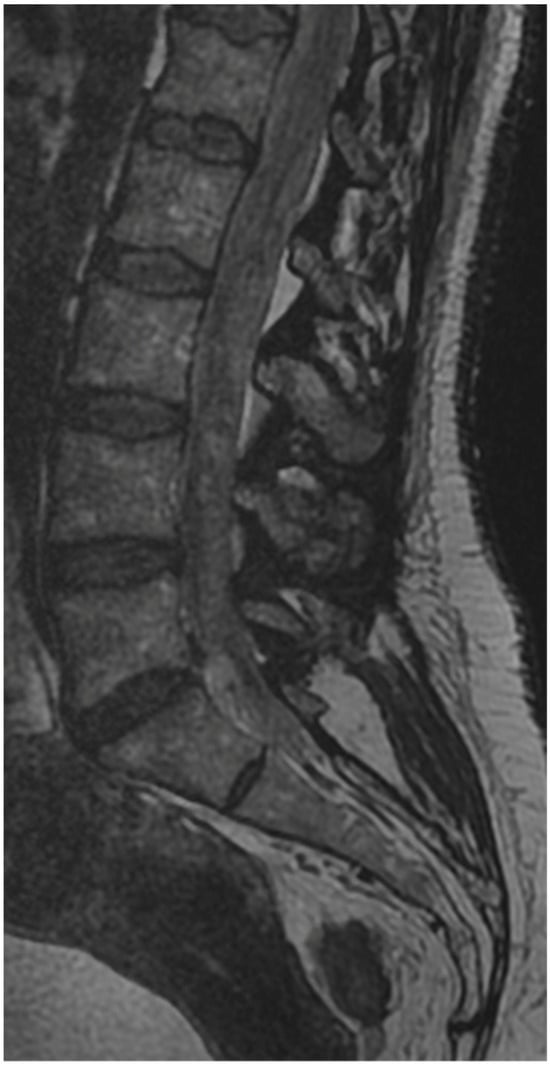

3.4. Case 1: Transient Cauda Equina Syndrome Due to Subdural Hematoma